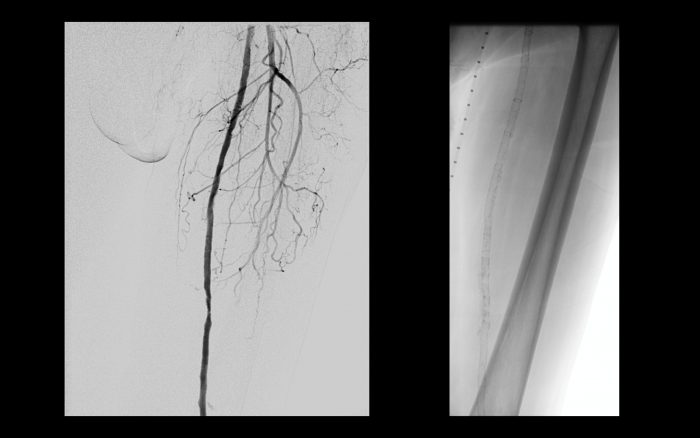

Após cerca de 1 ano, o paciente evolui com claudicação intermitente para curtas distâncias predominando do membro inferior direito.